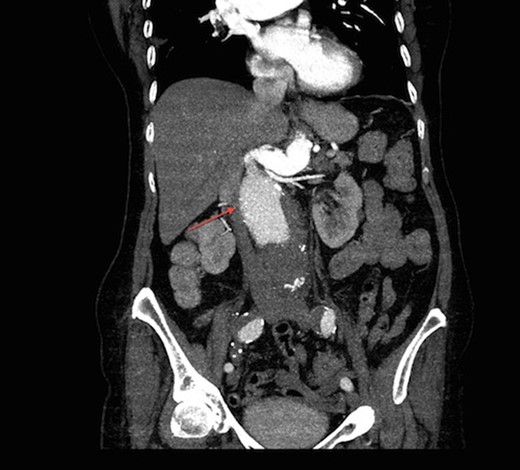

On arrival at our hospital, she was hemodynamically stable, with all vital signs within the normal range. Abdominal examination revealed a pulsating mass in the center of the abdomen. A computed tomography (CT) angiogram of aorta was performed for further evaluation that showed ectatic aorta from arch to the diaphragm. There was an 8.7-cm infra-abdominal AAA with extension into both common iliac arteries. The aneurysm neck was tortuous with an acute angle making endovascular repair challenging (Figs 1–4).

Transverse view of CT aortogram, showing compression of IVC (arrow).